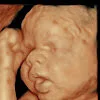

Watch Erica Mena and Safaree see their baby here at Haylo3d Feb 1 Written By Haydee longmore Haydee longmore